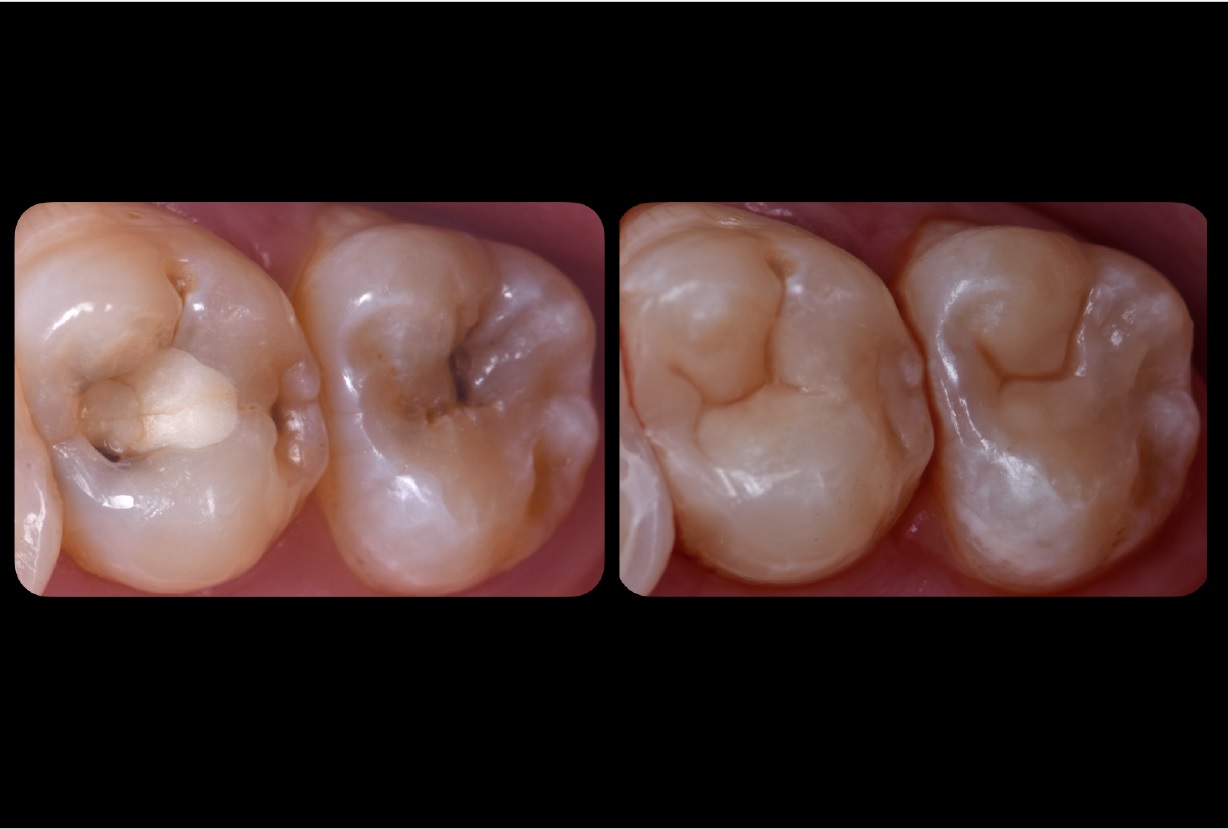

Εικ. 1: Ασθενής 21 ετών προσήλθε στην κλινική με ευαισθησία στο κρύο στο άνω δεξιό τεταρτημόριο. Η ενδοστοματική κλινική εξέταση αποκάλυψε μια παλιά, αποκατάσταση σύνθετης ρητίνης στον δεύτερο άνω γομφίο με ρωγμές και τερηδόνα στον τρίτο γομφίο. Η ακτινογραφία επιβεβαίωσε μια βαθιά τερηδονική αλλοίωση στον τρίτο γομφίο και την παρουσία μιας κατεστραμμένης αποκατάστασης σύνθετης ρητίνης στον δεύτερο γομφίο.

Εικ. 10: Το τελικό αποτέλεσμα αμέσως μετά την αφαίρεση του ελαστικού απομονωτήρα. Στη συνέχεια, ελέγχθηκε η σύγκλειση και η αποκατάσταση σύνθετης ρητίνης στιλβώθηκε.

Εικ. 17: Η αρχική κατάσταση και το τελικό αποτέλεσμα και των δύο αποκαταστάσεων